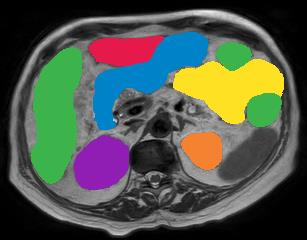

Vision transformers, with their ability to more efficiently model long-range context, have demonstrated impressive accuracy gains in several computer vision and medical image analysis tasks including segmentation. However, such methods need large labeled datasets for training, which is hard to obtain for medical image analysis. Self-supervised learning (SSL) has demonstrated success in medical image segmentation using convolutional networks. In this work, we developed a \underline{s}elf-distillation learning with \underline{m}asked \underline{i}mage modeling method to perform SSL for vision \underline{t}ransformers (SMIT) applied to 3D multi-organ segmentation from CT and MRI. Our contribution is a dense pixel-wise regression within masked patches called masked image prediction, which we combined with masked patch token distillation as pretext task to pre-train vision transformers. We show our approach is more accurate and requires fewer fine tuning datasets than other pretext tasks. Unlike prior medical image methods, which typically used image sets arising from disease sites and imaging modalities corresponding to the target tasks, we used 3,643 CT scans (602,708 images) arising from head and neck, lung, and kidney cancers as well as COVID-19 for pre-training and applied it to abdominal organs segmentation from MRI pancreatic cancer patients as well as publicly available 13 different abdominal organs segmentation from CT. Our method showed clear accuracy improvement (average DSC of 0.875 from MRI and 0.878 from CT) with reduced requirement for fine-tuning datasets over commonly used pretext tasks. Extensive comparisons against multiple current SSL methods were done. Code will be made available upon acceptance for publication.